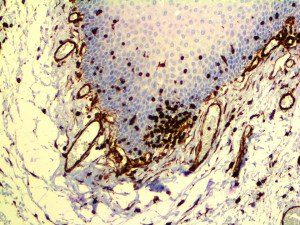

The first cytokines released are interleukin 1β (IL-1β) and tumor necrosis factor-α (TNF-α), which attract a variety of circulating white blood cells (WBCs) to the infection site, including neutrophils, monocytes, macrophages, and natural killer (NK) cells. This response, along with the antipathogenic chemicals released by these cells (i.e., complement), comprise the innate immune response. These cells directly attack the invading pathogen and also release additional cytokines, chief among them interleukin-1 and 6 (IL-6). IL-6 is essential for invoking the adaptive immune response, which calls T-cells, B-cells, and T helper (Th) cells to the infection site. IL-6 also stimulates further recruitment, proliferation and activation of macrophages.

This activation induces inflammatory monocytes to highly express IL-6, starting a localized and then systemic cascade effect that results in hyperproduction of IL-6, which accelerates the inflammatory process. Because IL-6 also increases vascular permeability, excessive levels cause blood vessels to become very leaky. This, along with clotting factors released from vascular endothelial cells, stimulates the coagulation cascade, resulting in microthrombosis (tiny clots), which leads to ischemia and tissue death of the kidney, intestines, heart, liver, brain and extremities.